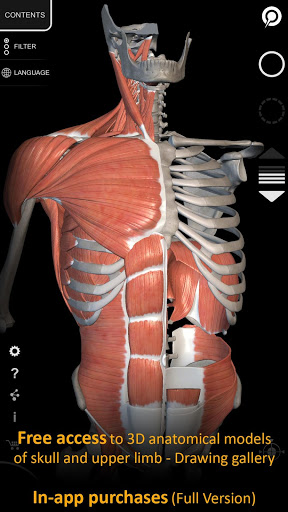

يتيح لك "Anatomy 3D Atlas" دراسة التشريح البشري بطريقة سهلة وتفاعلية.

من خلال واجهة بسيطة وبديهية، من الممكن ملاحظة كل بنية تشريحية من أي زاوية.

تتميز النماذج التشريحية ثلاثية الأبعاد بتفاصيل خاصة ودقة تصل إلى 4K.

نماذج تشريحية ثلاثية الأبعاد

• الجهاز العضلي الهيكلي